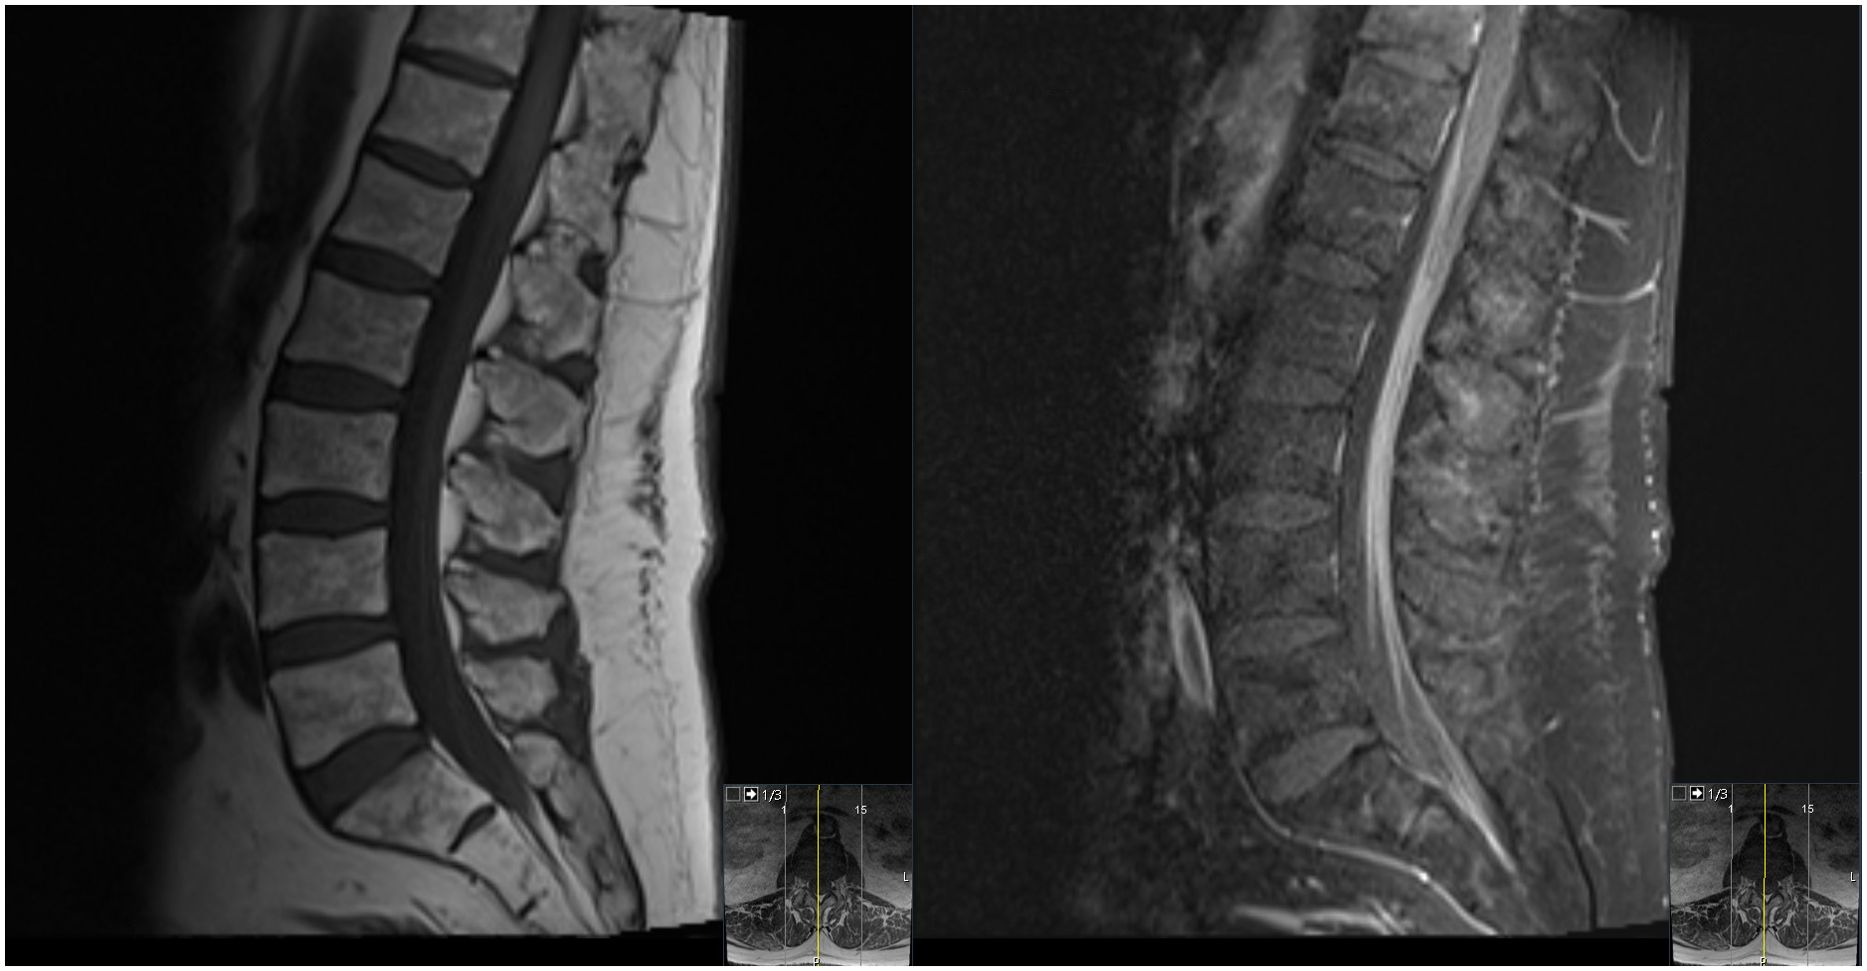

At the end of this period, the patient presented to multiple providers with complaints of generalized weakness and fatigue. These symptoms were accompanied by intermittent hearing difficulties/ear fullness/tinnitus as well as periods of left lower extremity weakness. A referral to audiology revealed no hearing loss. In the interim, he developed fevers, worsening headaches, and burning neuropathic back pain that radiated down both legs. He sought emergency medical treatment, where he was noted to have ⅘ strength throughout bilateral lower extremities accompanied by areflexia, but no sensory deficits. Imaging was notable for extensive cauda equina enhancement without vertebral involvement (see Figure 1), suspicious for Guillan-Barre Syndrome. Lumbar puncture revealed >3000 WBCs with 97% CD34+ myeloblasts (see Table 1), elevated protein, and decreased glucose. Molecular studies were sent, but were difficult to analyze given the small quantity of cells and a low mitotic index. Ultimately, both the cytogenetic and immunophenotypic results of the CSF (see Figures 2, 3) were unchanged from those found in the marrow during the first relapse.

Figure 1. T1-weighted midsagittal lumbar spine MRI with precontrast (left) and postcontrast (right) images showing diffuse enhancement of the cauda equina rootlets.